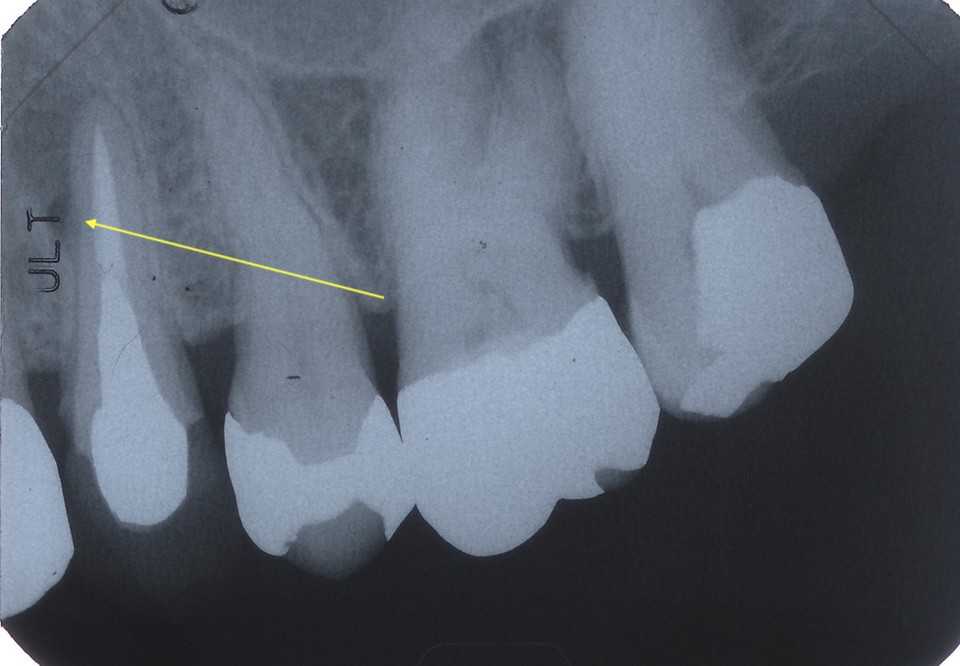

50代女性、左上5-7ブリッジ脱離、7番2次カリエス+Per(根尖性歯周炎)、強度の外傷性咬合この方、ひどい食いしばりで歯が壊れてしまう。噛み合わせの左下7番も歯冠が崩壊しつつある。7番はブリッジが脱離していて、内部は虫歯でドロドロ。Perつまり根管充填が緊密ではなく、歯根内部は細菌だらけで根の周りにはひどい炎症がある。まずはレントゲン写真から。7番の歯根の周りが炎症で黒くなっているのが分かると思う。ブリッジを全部外すと咬合が狂うので、とりあえず7番だけカットして内部を見てみた。根管充填材が見えるところまで軟化象牙質を除去して、3MIX+α-TCPを入れて根管内部を殺菌することにした。根管充填材の周りは黒くなっているのが見えると思うが、これは硫酸塩還元細菌の代謝産物の硫化鉄:FeSで、理想に反して根管充填材はゆるゆるの緊密充填ではないことを示している。このような状況は普通のことだ。歯根内部は細菌だらけということだが、ゆるゆるだから根管充填材を全部除去する必要もない。ゆるゆるの隙間から3MIX(抗菌剤)は浸透し根管は殺菌される。外傷力を弱めるために咬合調整を繰り返している。コア部分は隙間に細菌由来の黒色物質FeSがこびりつき、真っ黒。ポンティック下も細菌のコロニーでドロドロ歯質は残っているように見えるかもしれないが、ボンディング材が効く程度に軟化象牙質(虫歯)を除去すると、残根状態になる。つまり通常治療では抜歯しかないということだ。しかもPerでグラグラの動揺度2〜3、垂直性同様有りだ。とてもこのままではブリッジの支台には使えそうもない。ピンク色の根管充填材が見えると思うが、周りは真っ黒だ。その真っ黒になった隙間から細菌は侵入するし、3MIXも浸透する。こうではない緊密な根管充填治療は垂直加圧法でしか見られない。3MIX+α-TCPCR(ダイレクトボンディング)で覆う。これでないと微小漏洩が起こり失敗する。丸い形はラウンデッド・コアと呼び、この形が咬合力を内向きに集中させ歯根を守る。ポストは歯根の外側にこじるような応力を生じるので歯根を壊してしまいやすい。補綴物が必要な時はピンレッジで維持力を得る。これはCAD/CAMでは作れないだろう。これで2〜3週間様子をみる。外傷性咬合のコントロール(ナイトガードや行動療法)をしながら。つづく